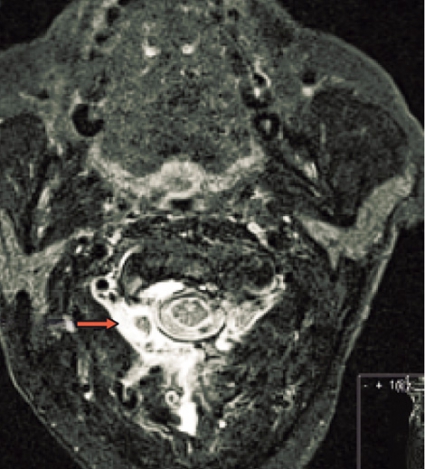

Spontan intrakraniell hypotension är sannolikt ett underdiagnostiserat tillstånd som man bör tänka på hos patienter med nytillkommen daglig huvudvärk, särskilt om den förvärras i stående (Fakta 1). För att ställa diagnos gäller att likvortrycket ska vara lågt, helst <6 cm H2O i liggande, och MRT med kontrast (helst före lumbalpunktion) ska visa generell dural uppladdning (s k pakymeningit) och karakteristiska förändringar av hjärnstammen (Fakta 2) [1, 2]. Initial behandling är symtomlindring med sängläge och gradvis mobilisering. Den kompletteras ofta med rikligt vätskeintag och koffein, antingen i tablettform eller som dropp. Om detta inte ger effekt är epidural injektion av autologt blod (»blood patch«) nästa steg, som ger snabb effekt hos de flesta patienter men som kan behöva upprepas [3]. Vid terapiresistens övervägs utvidgad neuroradiologisk utredning för att lokalisera likvorläckagestället. Då finns möjlighet att upprepa blodinjektionen över själva läckagestället. Om det inte hjälper kan kirurgiskt ingrepp diskuteras [2]. Etiologi och patogenes År 1938 beskrev den tyske läkaren Georg Schaltenbrand det tillstånd som kom att kallas spontan intrakraniell hypotension [4, 5]. Då trodde man att orsaken var minskad produktion av likvor från plexus choroideus eller ökad absorption, men bevis saknades. I dag vet man att tillståndet beror på likvorläckage, sannolikt på grund av en defekt i dura mater. Vid utredning har man kunnat påvisa spinala epidurala cystor (divertiklar) som bedömts ha rupturerat spontant eller vid en plötslig tryckstegring i likvorrummet. Det är också känt att osteofyter och diskbråck kan orsaka läckage genom att erodera duran [6, 7]. I dessa fall kan operation bli nödvändig [8]. Vid kirurgi kan man se många olika durala avvikelser, såsom rifter och meningeala cystor [9-11]. Spontan intrakraniell hypotension uppkommer förmodligen i vissa fall av en kombination av lindrigt trauma och underliggande spinal patologi [2, 12]. Enligt litteraturen har upp till en tredjedel av patienterna en oupptäckt bindvävssjukdom. Många har morfologiska tecken på bindvävssjukdom, såsom lång och smal kroppsbyggnad, spindelfingrar och överrörlighet i lederna [13, 14]. I de flesta fall är dock bindvävssjukdomen ospecifik, och endast i ca 5 procent av fallen har en specifik diagnos kunnat ställas, såsom Marfans syndrom eller Ehlers–Danlos syndrom typ II [13, 15-17]. Familjär spontan intrakraniell hypotension har även beskrivits [18]. Det är viktigt att veta att ett normalt spinalt öppningstryck (7–20 cm H2O) inte utesluter diagnosen [12]. Hos en patient med normalt tryck är det symtomen och tecknen på MRT som ger diagnosen. Många menar att förlust av likvor är den verkliga orsaken till syndromet och att hypotensionen är en följd av hypovolemin [19]. Likvorhypovolemisyndrom (CSF hypovolemia syndrome) har därför föreslagits som ett nytt namn på tillståndet [19]. Läckagestället är nästan alltid beläget i cervikotorakala delen, ofta i cervikotorakala övergången [12]. I praktiken kan det vara svårt att fastställa ett exakt läckageställe. Ofta samlas vätska bakom durasäcken i höjd med kotkropparna C1–C2 [20]. Denna vätskeansamling är dock inte ett säkert tecken på läckage från detta område. Det kan vara en falsk lokalisation. Sannolikt kommer läckaget från en annan nivå, och vätskan förflyttas uppåt till övre halsryggen [20]. Ibland kan man se multipla läckageställen samtidigt [21]. Epidemiologi Spontan intrakraniell hypotension har länge ansetts vara mycket sällsynt. Men kanske är tillståndet inte så ovanligt. Inga säkra siffror från samhällsbaserade studier finns tillgängliga för att beräkna incidensen och prevalensen. I en studie av radiologiska undersökningar på en akutavdelning diagnostiserades sjukdomen ungefär hälften så ofta som spontan subaraknoidalblödning – med en uppskattad årlig incidens på 5/100 000 [22]. På ett sjukhus i Rom diagnostiserades 82 patienter under en 18-årsperiod, 1992–2009, av vilka 40 behandlades konservativt med sängläge och 42 med lumbal epidural injektion av autologt blod [3]. På vår klinik har vi haft 10–15 patienter med detta tillstånd de senaste fyra åren. Den högsta incidensen av spontan intrakraniell hyptension ses vid vid ca 40 års ålder, men fall har beskrivits hos personer mellan 3 och 86 års ålder. Sjukdomen tenderar att drabba kvinnor något oftare än män (kvot ca 1,5:1) [2]. Kliniska symtom Den vanligaste kliniska manifestationen av spontan intrakraniell hypotension är ortostatisk huvudvärk, som förvärras gradvis med maximal intensitet efter flera minuter till timmar. Det händer att huvudvärken debuterar plötsligt. Man misstänker då ofta subaraknoidalblödning, och patienten utreds av denna anledning [23]. De allra flesta patienter kan minnas dagen då huvudvärken började, om än inte den exakta tidpunkten. Huvudvärken brukar beskrivas som diffus, pulserande eller icke-pulserande och är vanligen lokaliserad till nackregionen men kan också vara frontotemporal. Huvudvärken behöver inte vara symmetrisk men är sällan helt ensidig. Hur allvarlig huvudvärken är varierar, och det är troligt att en del lindriga fall förblir oupptäckta och att läkning sker spontant. En ledtråd till diagnosen kan vara om patienten beskriver en dragningskänsla från huvudet ner till nacken. Ytterligare ledtrådar är om patienten föredrar att ligga ned på undersökningsbritsen eller har en kudde med sig [2]. Även om ortostatisk huvudvärk är det kliniska kännetecknet, vilket återspeglas i alla diagnostiska kriterier, är det välkänt att den ortostatiska komponenten ofta blir mindre framträdande eller försvinner med tiden. Dessutom har patienter vars huvudvärk från början har saknat ortostatisk komponent beskrivits [24, 25]. Den exakta orsaken till huvudvärken är inte känd, men man antar att det är förlusten av likvor som orsakar neddragningen av hjärnan med sekundär dragning av smärtkänsliga intrakraniella strukturer [12]. En alternativ förklaring är att det sker en kompensatorisk dilatation av smärtkänsliga intrakraniella venösa strukturer. Förutom huvudvärk har många andra symtom rapporterats. De vanligaste, som förekommer i mer än hälften av fallen, är nacksmärta eller nackstelhet, illamående och kräkningar. Upp till hälften av patienterna beskriver lockkänsla eller tinnitus, och ca 10 procent uppvisar kranialnervspåverkan (vanligtvis abducenspares) med dubbelseende [12]. Abducensnerven har en lång och komplicerad väg intrakraniellt och är därför särskilt utsatt. MRT-undersökning av hjärnan MRT har revolutionerat inte bara erkännandet av sjukdomen utan också förståelsen av den [2]. MRT har i hög grad underlättat möjligheten att komma fram till en säker diagnos utan att behöva använda ingrepp som lumbalpunktion. MRT är förmodligen den viktigaste faktorn bakom det ständigt ökade antalet patienter med spontan intrakraniell hypotension sedan början av 1990-talet [2]. Det typiska fyndet vid cerebral MRT är generell pakymeningit (Figur 1). Pakymeningit i samband med spontan intrakraniell hypotension beskrevs första gången år 1991 av Mokri et al [26]. Det är dock viktigt att veta att upp till 20 procent av patienterna med spontan intrakraniell hypotension inte har någon tydlig pakymeningit [27]. Man tror att den meningeala förtjockningen beror på dural vasodilatation. Grunden för detta är Monroe–Kellie-doktrinen, enligt vilken summan av intrakraniellt blod, likvor och hjärnvävnad ska vara konstant i ett intakt kranium. Det innebär att minskningen av likvor leder till kompensatorisk vasodilatation [12, 19]. De flesta av förändringarna som ses vid MRT kan förklaras av dessa kompensatoriska mekanismer med pakymeningeal uppladdning, vidgning av venösa strukturer och hypofysförstoring. »Sagging«, eller neddragning, av hjärnan är ett typiskt radiologiskt fynd vid spontan intrakraniell hypotension (Figur 2). Det ses tydligast på en sagittal MRT-bild med neddragning av hjärnstam och lillhjärnstonsiller genom foramen magnum som vid Chiari-missbildning typ 1 (Figur 2). Subdural vätska (effusioner och hematom) förekommer hos ca 50 procent av patienterna (Figur 3). Oftast är dessa vätskeansamlingar tunna, bilaterala och lokaliserade till ovanför storhjärnshemisfärerna, orsakade av bristningar i bryggvener, utan någon märkbar expansiv effekt. Vätskeansamling ses ibland i bakre skallgropen, särskilt över lillhjärnshemsifärerna eller bakom clivus. Dessa vätskeansamlingar brukar försvinna när behandling sätts in mot det underliggande spinala likvorläckaget 28]. Om kirurgin riktas endast mot vätskeansamlingarna utan att läckaget behandlas är risken för recidiv ganska stor. Hypofysär hyperemi med förstoring av körteln är ett annat radiologiskt tecken på spontan intrakraniell hypotension [29]. Förstoringen kan bli ganska anslående och kan likna en hypofystumör. Det finns många tillstånd som radiologiskt kan likna spontan intrakraniell hypotension. Den förtjockade kontrastladdade duran kan misstolkas som ett kroniskt subduralhematom, men i dessa fall ses i regel ett vätskespatium mellan uppladdningarna. Idiopatisk hypertrofisk pakymeningit ger oftare fokal, dural förtjockning och inte den jämna, kontinuerliga uppladdningen som vid hypotensionssyndromet. Framför allt gäller detta vid granulomatös meningit och meningeal karcinomatos, vilka också oftare drabbar de mjuka hinnorna än den hårda hjärnhinnan. Meningealt lymfom och durala metastaser liksom meningiom med »dural svans« har ofta associerade skelettförändringar. Vid alla ovan nämnda tillstånd saknas dessutom den typiska bilden av neddragen hjärna. Spinal MRT Spinal MRT kan visa områden med extradural vätskeansamling (särskilt vid C1–C2) (Figur 4 och 5), meningeala divertiklar, dilatation av epidurala vener, dural uppladdning och komprimerad durasäck [30-32]. DT-myelografi Lumbalpunktion med injektion av jodkontrast följt av DT-myelografi med tunna snitt och reformateringar av hela ryggraden har visat sig vara en bra metod för att definiera läckagets exakta lokalisering och omfattning. DT-myelografi har visat sig ha störst känslighet vad gäller att lokalisera läckagestället [32]. Icke-invasiva undersökningar som spinal MRT rekommenderas dock i första hand [33]. Myelografi med intratekal administration av gadolinium följt av MRT är ett alternativ som ibland används utomlands [34] men är ännu inte godkänd på indikationen spontan intrakraniell hypotension i Sverige. Lumbalpunktion Vanligtvis är öppningstrycket <6 cm H2O, och det kan vara omätbart. Det är dock väl dokumenterat att en del patienter med spinalt likvorläckage kan ha ett normalt öppningstryck [33]. Den förhöjda halten av protein och/eller förekomst av xantokromi beror troligen på ökad permeabilitet i dilaterade meningeala blodkärl. Behandling Även om detaljerade uppgifter saknas sker sannolikt spontanläkning i de flesta fall av spontan intrakraniell hypotension. Symtomlindring med sängläge och gradvis mobilisering är en väldokumenterad behandling [12]. Koffein och teofyllin har också visat viss effekt [12]. Om sängläge inte hjälper är den vanliga behandlingen injektion av autologt blod (10–30 ml) epiduralt i ländryggen [35]. Om behandlingen misslyckas kan den upprepas en till två gånger, och man kan då spruta in större mängder blod, upp till 40 ml. Med tanke på den potentiellt stora volymen blod som injiceras rekommenderas några dagars mellanrum vid upprepad behandling. Volymen blod som kan injiceras begränsas huvudsakligen av ryggsmärta eller radikulopati. Det rekommenderas att patienten bibehåller planläge efter injektionen för att minska likvorflödet genom duradefekten och därmed hjälpa till att stänga hålet. Det har diskuterats om injektion av autologt blod verkligen hjälper när läckagestället är på cervikotorakal nivå. En del rapporter finns som visar att behandlingen är effektiv [36, 37]. I den tidigare nämnda studien från Rom [3] behandlades 42 patienter med spontan intrakraniell hypotension på dettta sätt med stor framgång, trots att läckaget i de flesta fall var på cervikotorakal nivå. 38 patienter (90 procent) blev återställda efter ett ingrepp, 2 patienter (5 procent) efter två ingrepp och 2 patienter (5 procent) efter tre ingrepp. Författarna rekommenderar dock konservativ behandling under tio dagar innan blodinjektion ges. Romgruppen lät patienterna ligga i Trendelenburgläge 1 timme före och 24 timmar efter ingreppet. Intressant nog behandlade de patienterna med acetazolamid, 250 mg i tablettform, 18 och 6 timmar före ingreppet. Acetazolamid är en karbanhydrashämmare som minskar produktionen av likvor. Romgruppen för ett resonemang om huruvida premedicineringen och långvarigt Trendelenburgläge kan minska likvorflödet genom duradefekten och därmed hjälpa till att stänga hålet. Dessutom kan premedicineringen minska risken för återuppkomst av tillståndet [38]. Om den lumbala blodinjektionen inte hjälper kan man försöka injicera blod eller fibrinlim (Tissel) direkt över läckagestället. Dessa behandlingar kräver att läckagestället är känt. Placering av fibrinlim ger förmodligen den bästa symtomlindrande effekten [39]. När konservativ behandling och blod eller fibrinlim inte ger effekt kan kirurgi vara ett alternativ [8, 12]. Kirurgi innebär bl a ligering av meningeala divertiklar, packning med spongostan, fibrinlim eller gelskum i epidurala rummet, suturering av durarifter samt resektion av osteofyter och diskbråck. Prognos Långtidsuppföljningarna av naturalförlopp och behandlingsresultat är knapphändiga, men spontan intrakraniell hypotension tros återkomma hos ca 10 procent, oavsett behandling. Patienter med en radiologisk bild som är typisk för spontan intrakraniell hypotension och med känt läckageställe har utmärkt prognos, medan personer med normal MRT-undersökning och diffus spinalt likvorläckage på flera nivåer tycks ha sämre prognos [2]. Vissa patienter har kvarstående symtom efter behandling trots dokumenterat upphävt likvorläckage. Dessa patienter är svåra att behandla, och det är oklart om de har förändrad likvordynamik eller kanske små rester av likvorläckage som inte syns på röntgenbilder. * Potentiella bindningar eller jävsförhållanden: Inga uppgivna.